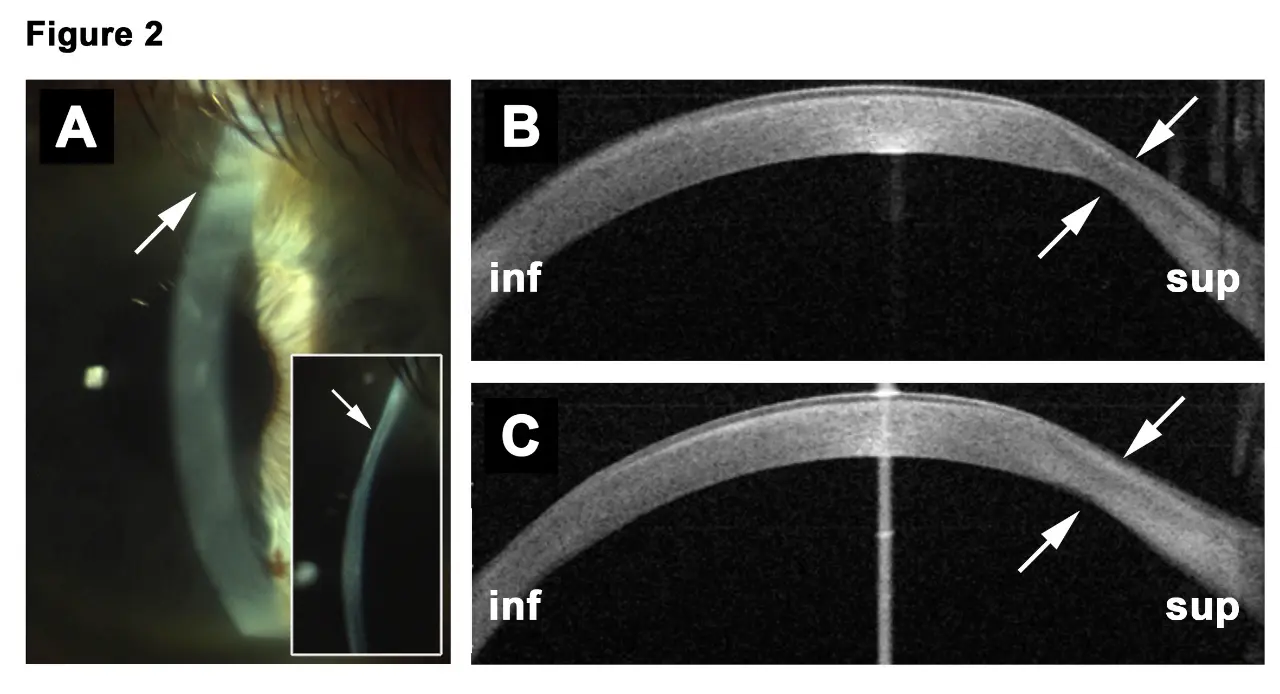

“We only treated two eyes, but it was the first time a Terrien could be stopped and partially reversed,” Farhad Hafezi, MD, PhD, OSN Europe Edition Board Member, said in a telephone interview with Ocular Surgery News